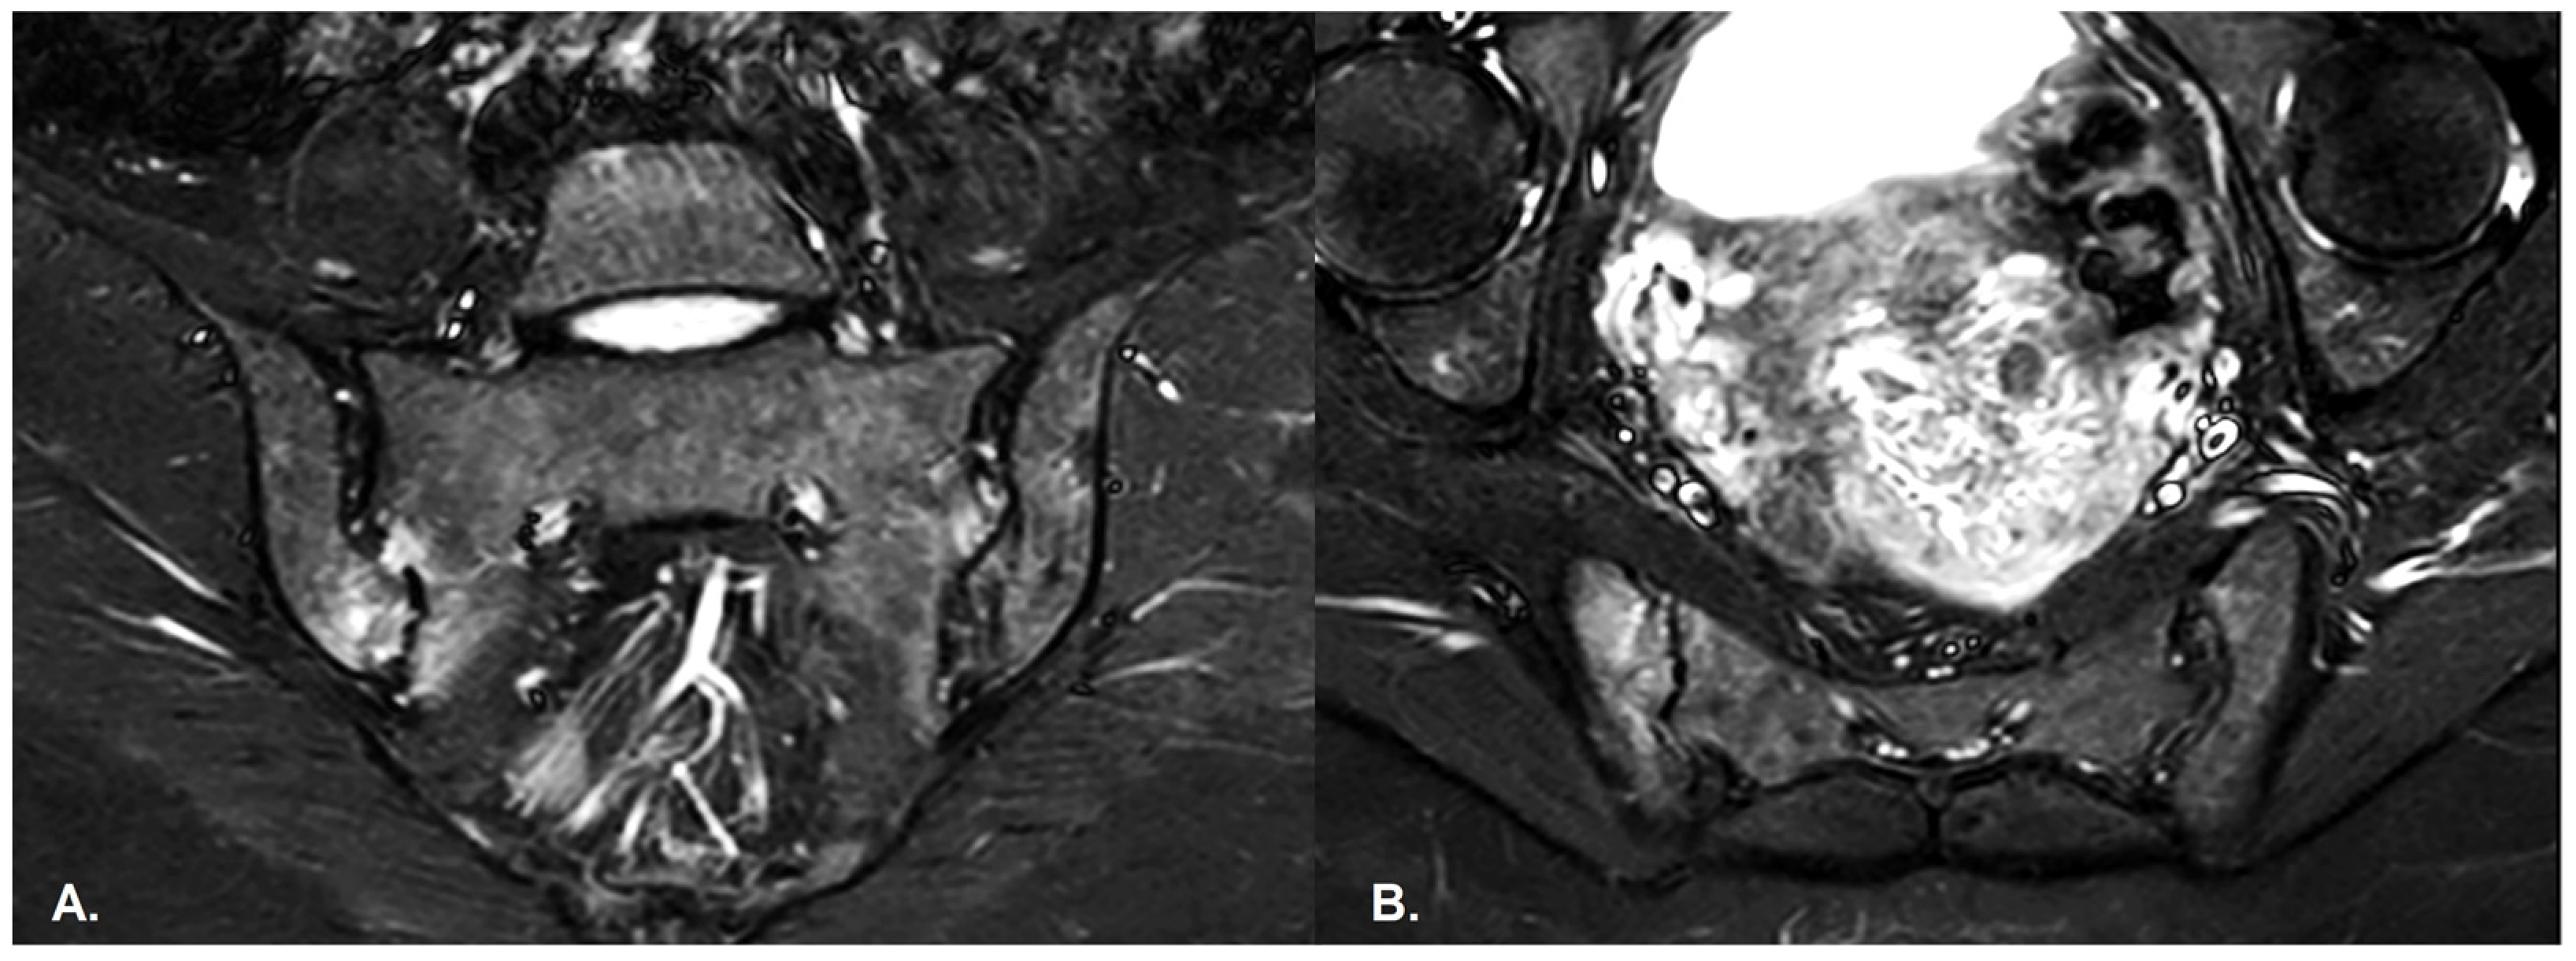

- BME is evident in low signal T1w, hyper signal T2w, STIR images and +C T1w Fat-Sat, similar to blood vessels and spinal fluid; the signal intensity is directly proportional to the inflammation activity. It is usually located periarticular to or on the subchondral bone surfaces and it is an indicator of disease activity (Figure 4) [65].

- Erosions–initially focal, later they will converge and will have a pseudo-enlargement aspect of the sacroiliac joint. In T1w images there is a loss of cortical bone signal (normally hypointense) and bone marrow fat (normally hyperintense).

- Sclerosis—better visualized on an X-ray or CT scan; a subchondral or periarticular area with a low signal compared to normal bone marrow on T1, T1FS (SPIR), and STIR sequences (Figure 5).Slight: <25% of the subcortical bone area.Moderate: 25% to <50% of the subcortical bone area.Severe: >50% of the subcortical bone area [29].